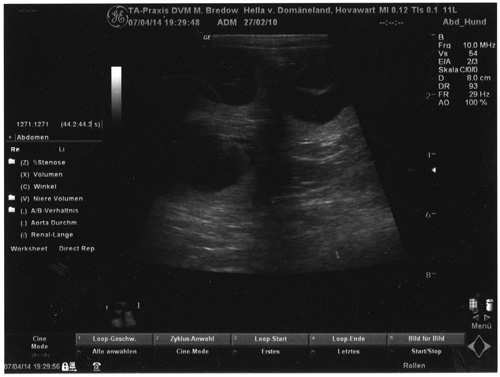

07.04.2014

-Ultraschall-

28.Tag |

Gute Nachrichten...

unsere Vermutung, die durch die Anzeichen der letzten Tage auf eine

Trächtigkeit hindeuteten (Verhaltensänderung, vergrößerte Zitzen usw.),

wurde heute bei der Ultraschalluntersuchung bestätigt. Hella ist tragend und

es wurden "viele" kleine Fruchtblasen lokalisiert. Hella ist gut drauf und

sie wiegt 32 kg - was ihrem Normalgewicht entspricht.

Die Embryonen oder ab jetzt Föten (die Embryonalperiode endet um den 28.Tag

rum) haben jetzt eine Größe von ca. 3 cm. Es sind bereits alle wichtigen

Organsysteme im Groben angelegt und die Körperform ist in Grundzügen

erkennbar. Zur Zeit äußerlich noch unscheinbar wird so ab der 5./6.

Trächtigkeitswoche das Größenwachstum der "Mini's" rapide zunehmen. |

Auf dem obigen Ultraschallbild sind drei

Fruchtblasen zu sehen |